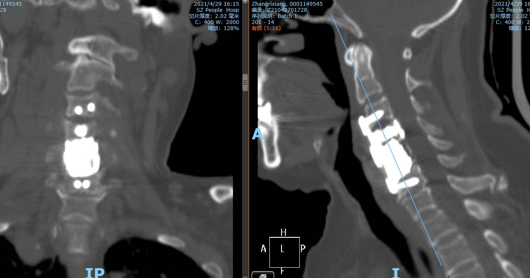

此为张阿姨术前颈椎CT骨窗,可以看见张阿姨的颈椎出现了被肿瘤破坏,侵蚀的表现。

此为张阿姨手术后的CT图像,可以看见张阿姨的椎体被骨水泥填充的同时,也进行了内固定处理,这样做不仅缓解了疼痛、破坏了肿瘤细胞,同时也对颈椎起到了强有力的固定。保持其稳定性。